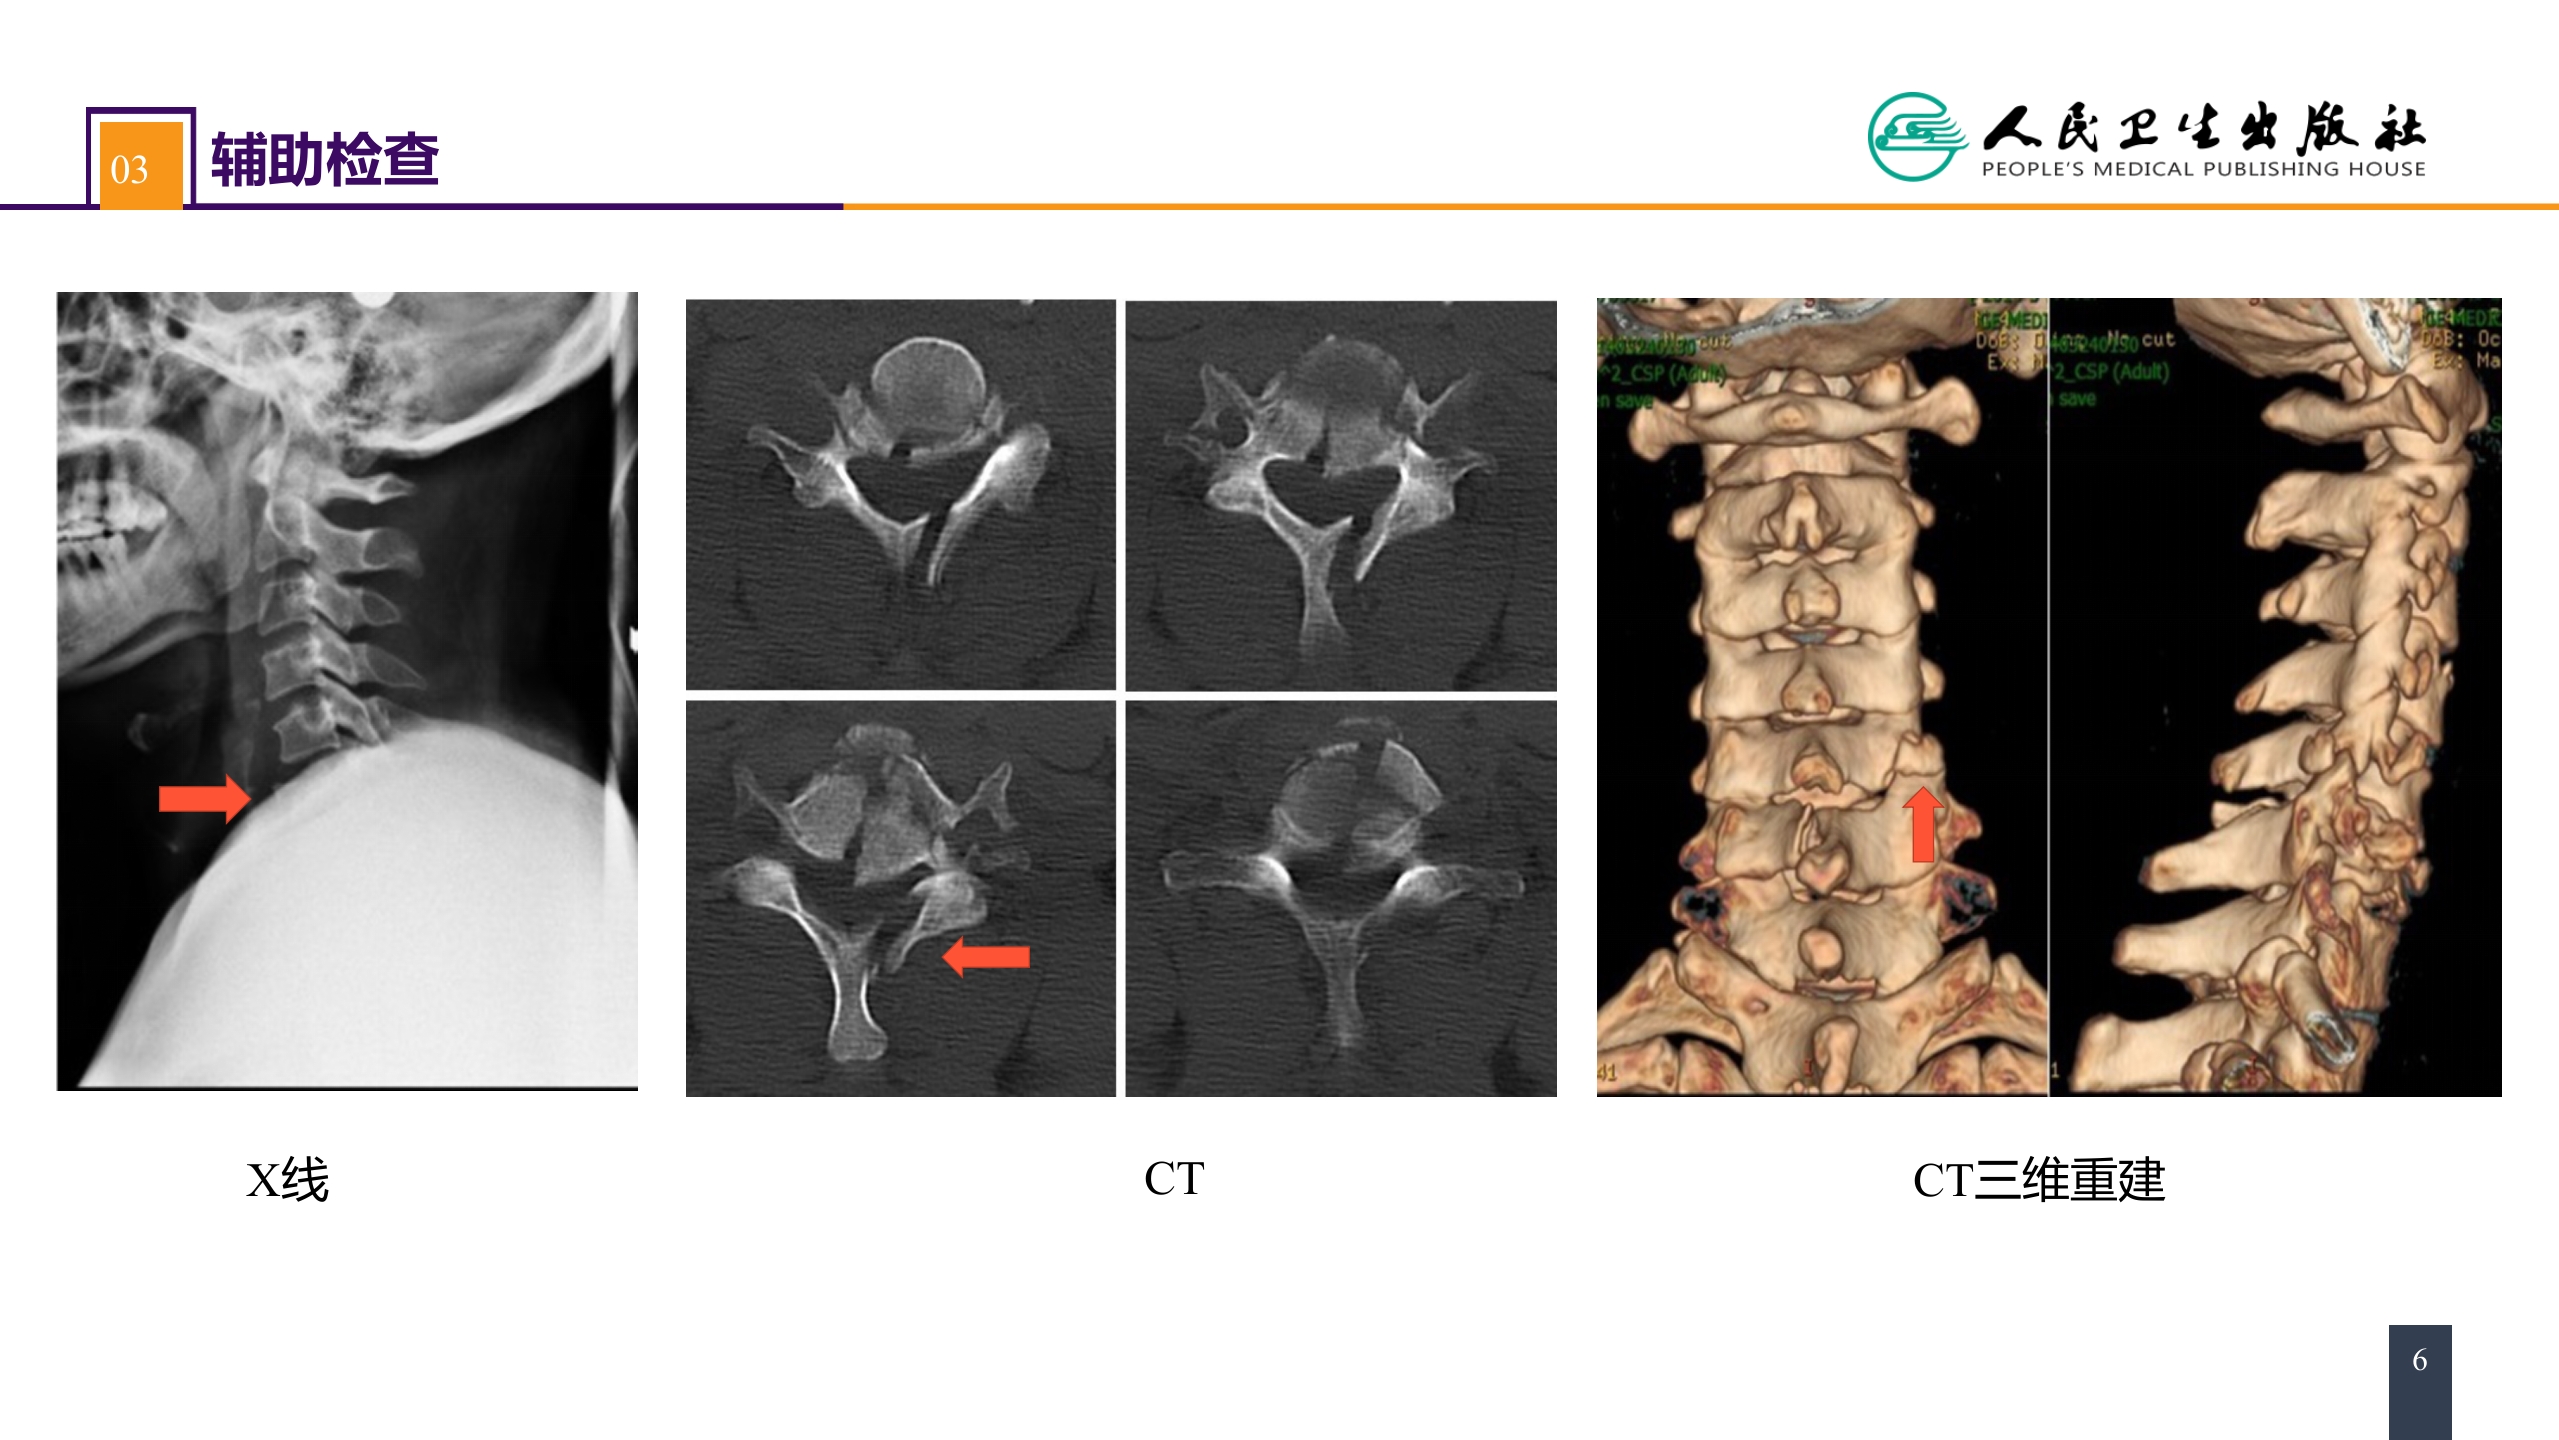

第六十二章 案例分析-颈椎骨折伴脊髓损伤